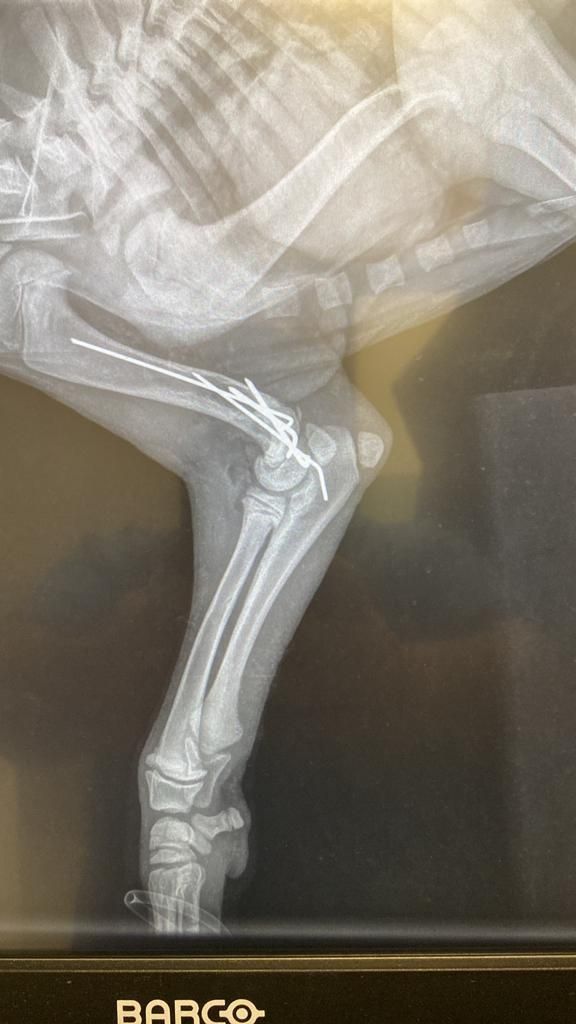

Aliki hat einen neuen Rüden in Obhut genommen. Dieser Hund, genannt Paok, ist ein Streuner, der in der Nähe ihrer Freundin Mareike lebte. Dort sind viele Häuser, viele Menschen, die ihn auch gefüttert haben. Eines Tages ist er aufgefunden worden, mit mehreren Knochenbrüchen. Die Gemeinde hat ihn aufgenommen und die Brüche operieren lassen.

Dann aber wurde er mal wieder sich selbst überlassen, und natürlich hat der Hund Schmerzen, so dass er den Gips aufgebissen hat. Aliki hat Mitleid mit dem armen Kerl und ihn erst mal aufgenommen. Sie wird versuchen, den Heilprozess in die richtige Richtung zu lenken, daher die Halskrause, die ein erneutes Aufbeißen verhindert. Aliki wird die Wunde täglich reinigen und so entzündungsfrei zu halten versuchen und Paok versorgen, bis er wieder zurück kann zu den Menschen, die ihn vorher bereits gefüttert haben. Anschließend wird sie sich darum kümmern, dass der Hund nun von der Straße ferngehalten wird. Aber erst heißt es einmal, dem armen Kerl die Daumen drücken und Aliki unterstützen, damit sie solche Hilfe Leistungen auch geben kann. 💙🥰

Update zu Paok 🐕🦺

Wir erinnern uns, dieser hübsche Streuner war in der Nähe von Mareike im März aufgegriffen worden, mit offenem Bruch, vermutlich ein Autounfall, er war von der Gemeinde operiert worden und dann zu Aliki gebracht worden. Der Tierarzt kam täglich, um den Nagel zu kontrollieren, dafür zu sorgen, dass die offene Wunde am linken Hinterlauf zuheilte. Dieser fröhliche, sehr zugewandte Hund nutzt leider sein Bein noch immer nicht, weshalb wir ihn dringend erneut vom Tierarzt untersuchen lassen wollen. Damit wir diese Kosten schultern können, suchen wir dringend Paten für Paok. Bitte helft uns! 🥰🐾💙